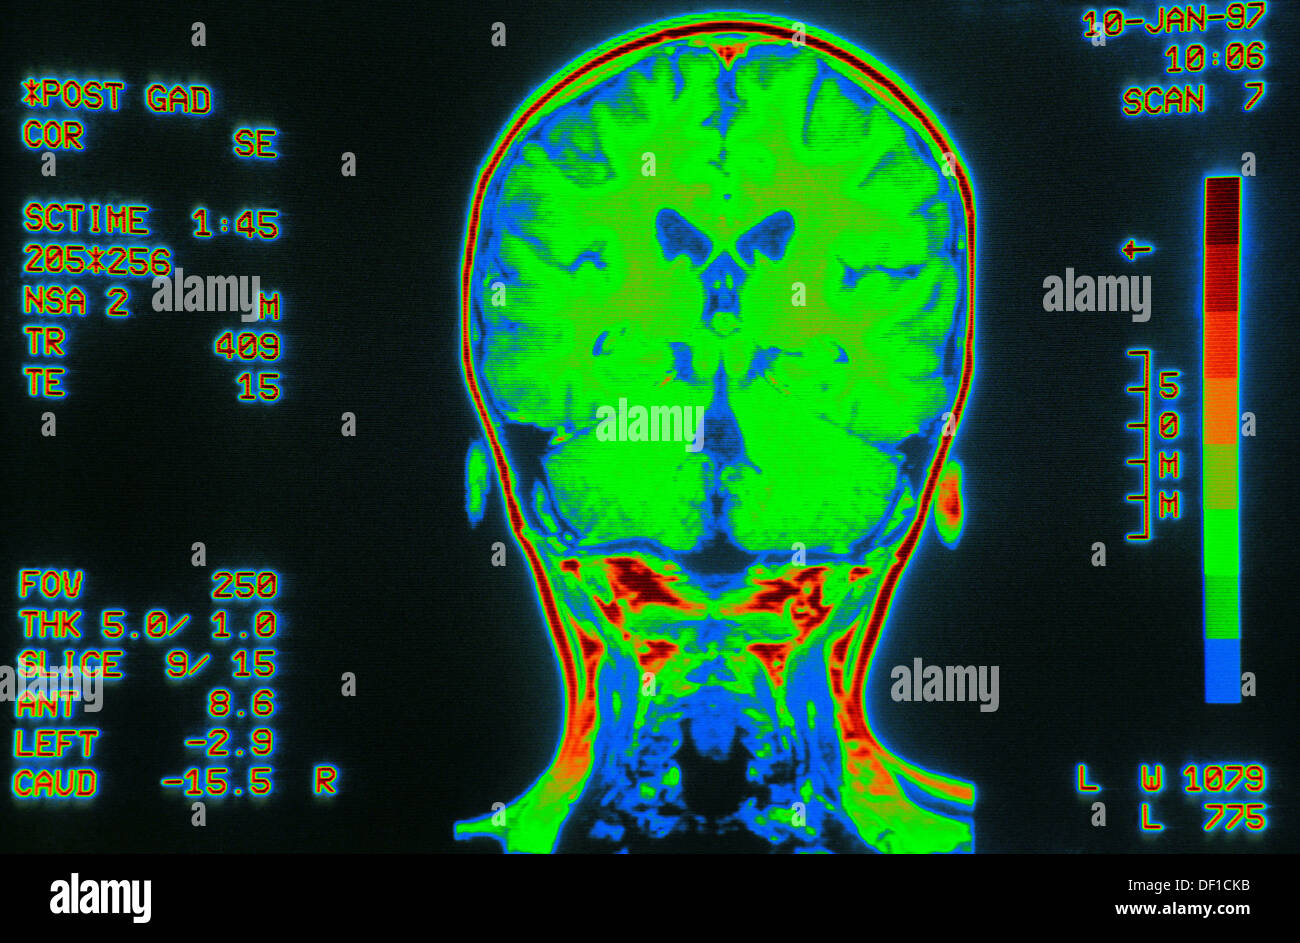

From www.alamy.com

Coloured MRI brain scan, back view Stock Photo 60882847 Alamy How Do I Know If I Need A Brain Scan table of contents. Brain scans may help evaluate head injuries,. a brain ct scan visualizes the structure of the brain and skull, and it can identify blood in and around the brain. A brain ct scan can also identify fluid, swelling, large tumors, or a large stroke. the term “brain scan” can refer to an mri scan,. How Do I Know If I Need A Brain Scan.